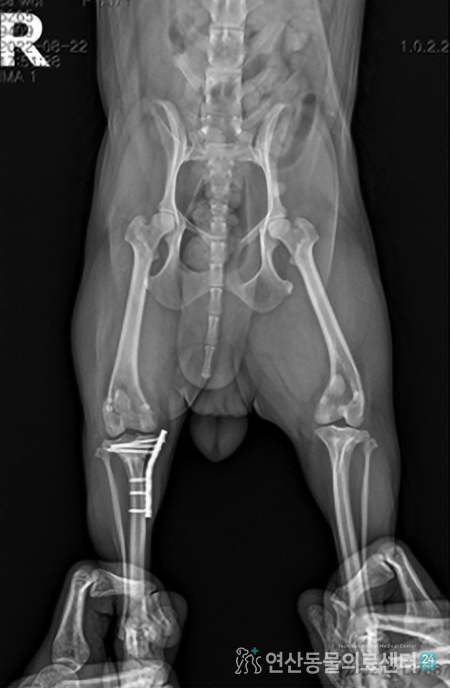

• 십자인대 수술 이미지

TPLO 십자인대 수술

절뚝거리는 증상으로 내원!

TPLO 수술 후 건강한 일상으로 복귀